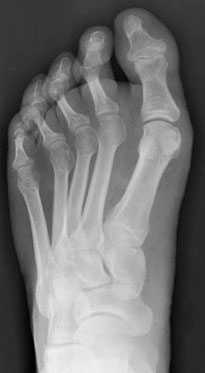

Добавочная ладьевидная кость классифицируется в соответствии с рентгенологическими ее особенностями:

- Сесамовидная косточка в толще сухожилия задней большеберцовой мышцы в области его прикрепления к ладьевидной кости

- Добавочная ладьевидная кость, сочленяющаяся синхондрозом с ладьевидной костью

- Костный выступ ладьевидной кости

Рентгенограмма стопы при 1 типе добавочной ладьевидной кости